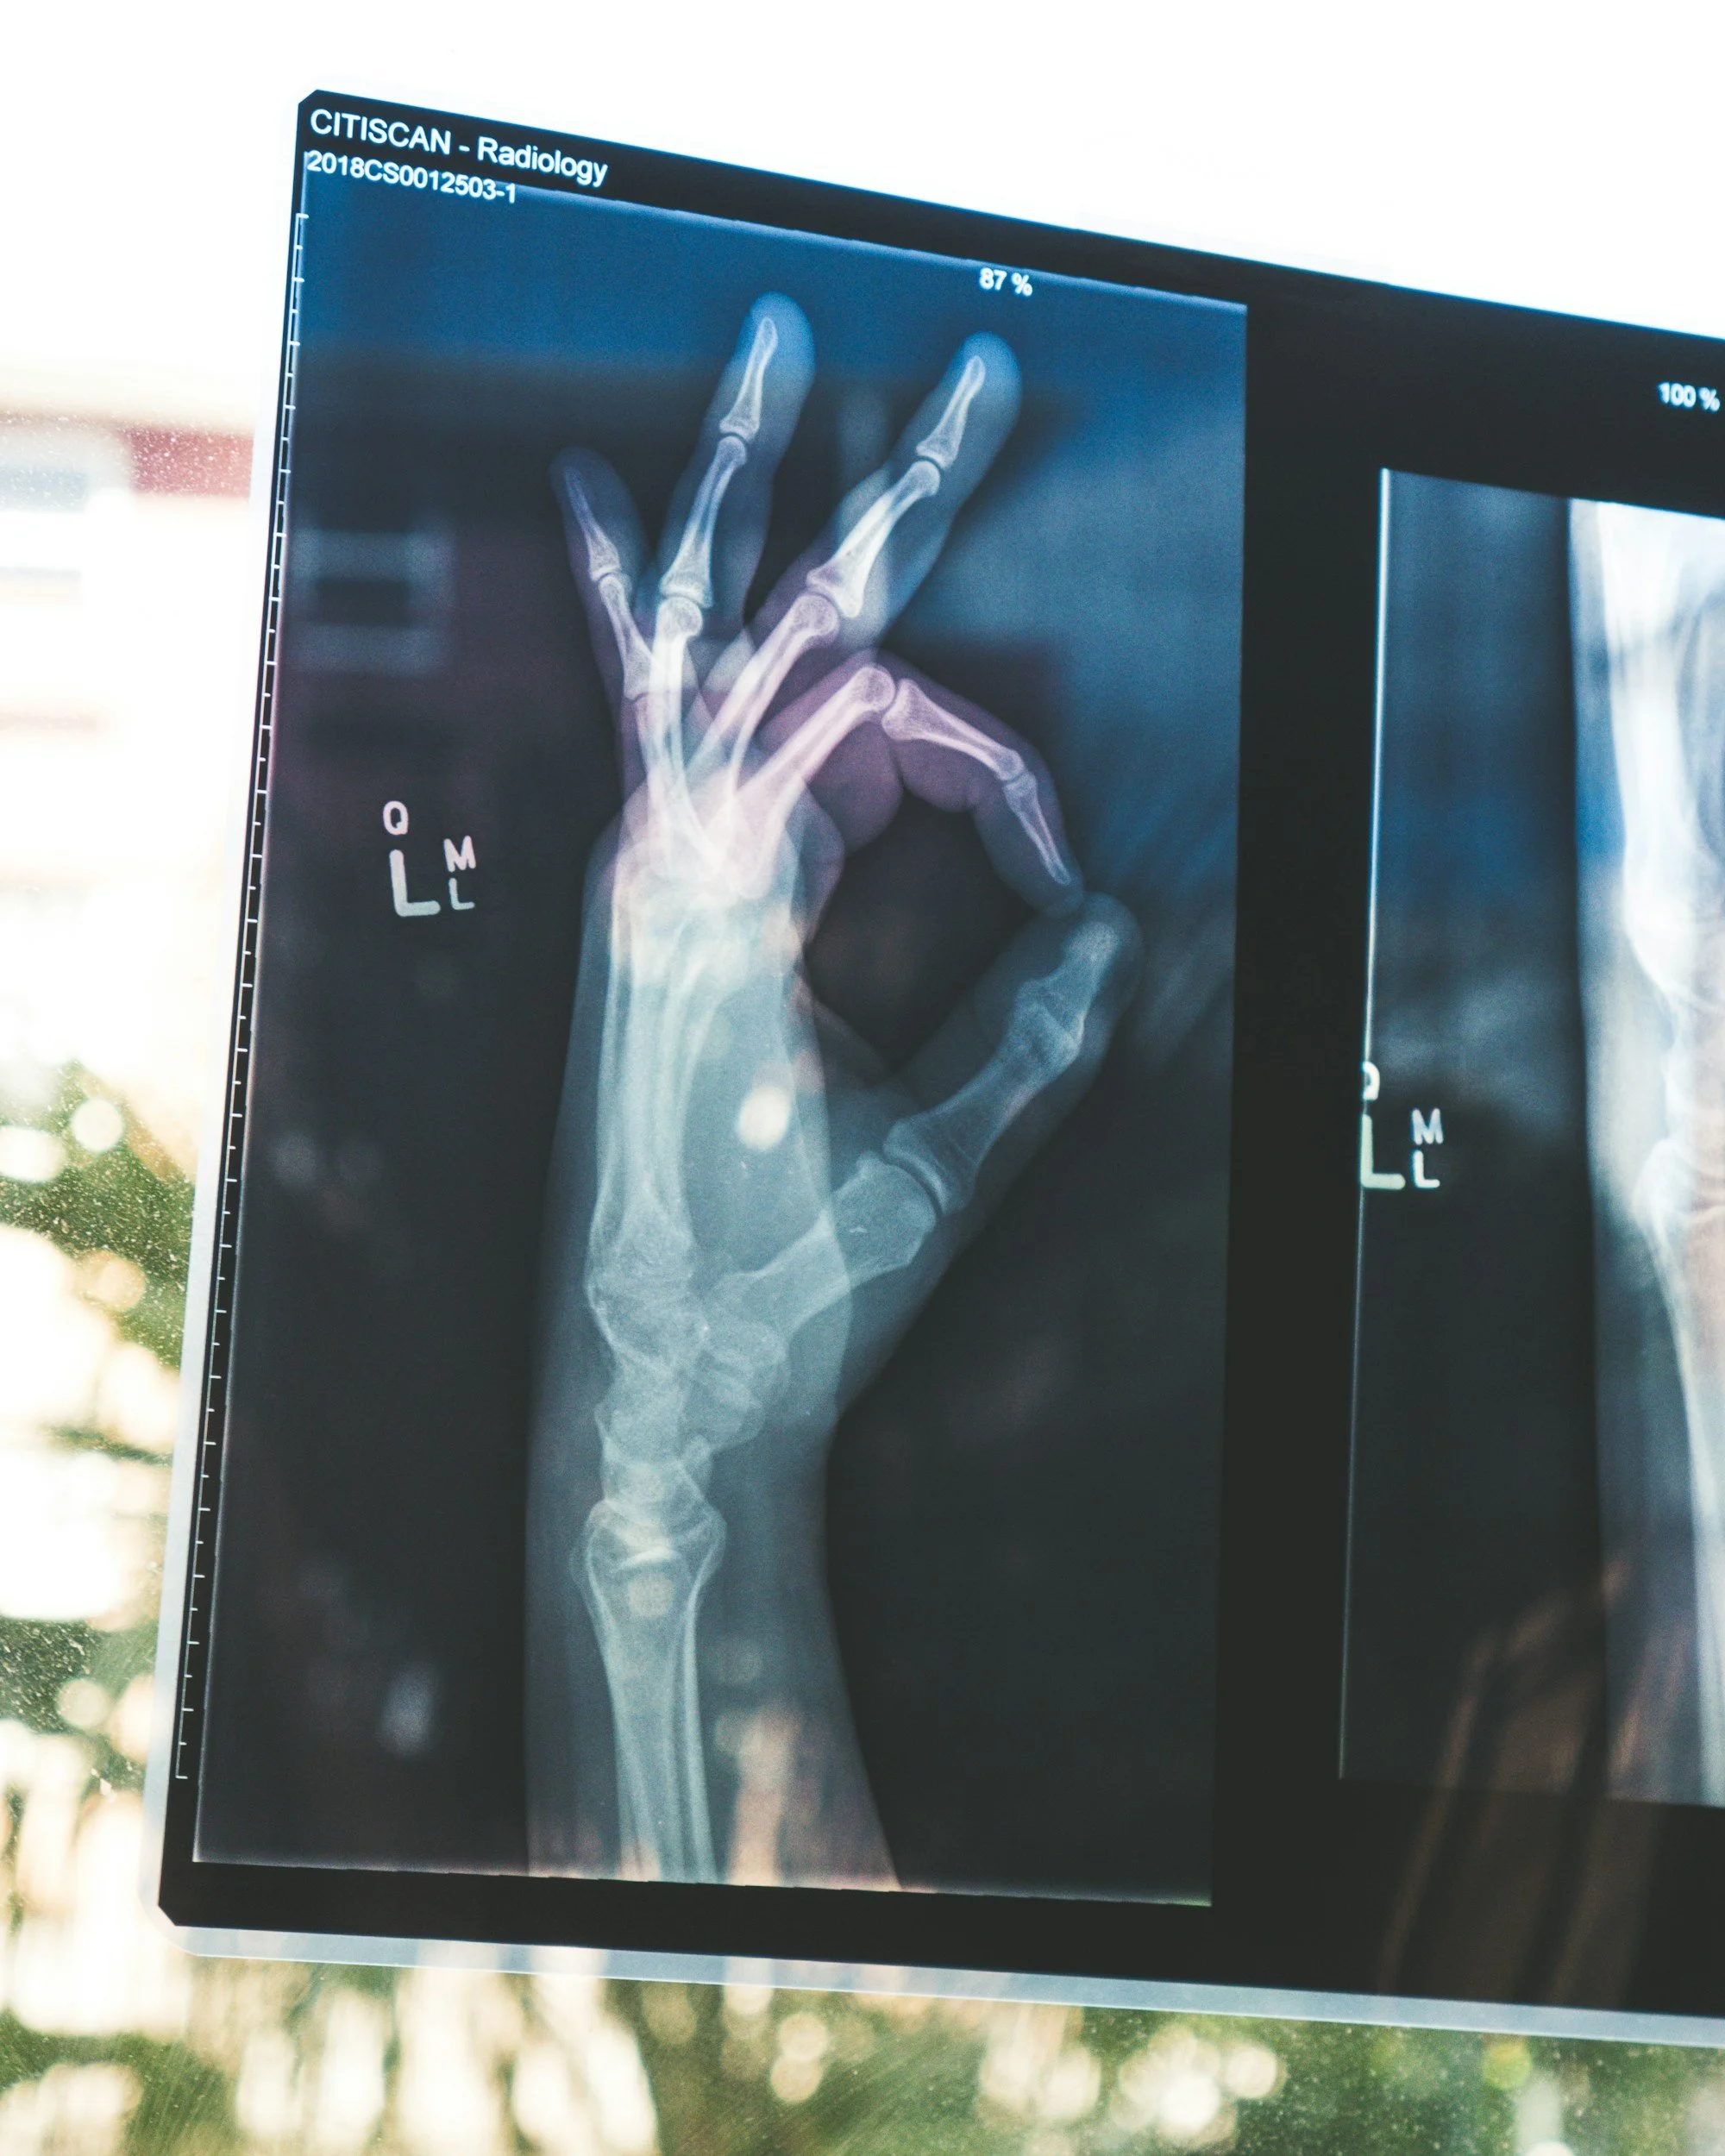

image of an Xray with an ok symbol for teaching about X-rays in the ER

An X-ray uses a small amount of radiation to create a two-dimensional image. Dense structures like bone absorb more radiation and appear white. Air appears black. Soft tissues fall somewhere in between.

It is not layered like a CT. It is not detailed like an MRI. It is essentially a shadow picture. But when you understand what shadows represent, they can reveal a great deal. Sometimes a shadow is all we need.

X-ray shines in specific situations. It is particularly strong for bones and lungs. If someone falls and cannot move their wrist, an X-ray quickly shows whether a fracture or dislocation is present. In the chest, it helps detect pneumonia, a collapsed lung, fluid around the lungs, and changes in heart size. It also confirms whether tubes and lines placed in emergencies are in the correct position.